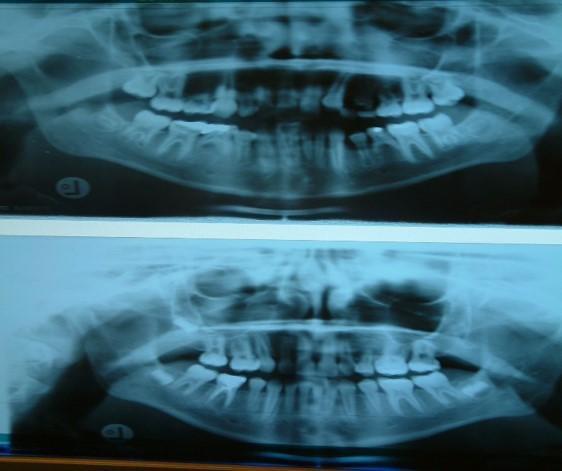

Στην ηλικία των 7 ετών, σύμφωνα με τις οδηγίες της Αμερικανικής Ορθοδοντικής Εταιρείας AAO (American Association of Orthodontics), καλόν θα είναι να εξετάζεται κλινικά αλλά και ακτινογραφικά η κατάσταση της μεικτής οδοντοφυίας του παιδιού για σκελετική ή οδοντική ασυμμετρία των γνάθων, για ελλείποντα δόντια ή δυνητικώς έγκλειστα ή για παρουσία οδοντωμάτων ή για έκτοπη ανατολή

Γενετικώς ελλείποντα δόντια (ο άνω αριστερός πλάγιος, ο άνω δεξιός 2ος προγόμφιος, οι κάτω δεύτεροι προγόμφιοι αμφοτερόπλευρα.)

Στα 7 χρόνια του παιδιού εξετάζουμε με πανοραμική ακτινογραφία τη θέση των μονίμων άνω κυνοδόντων στο οστό και αναλόγως πράττουμε.